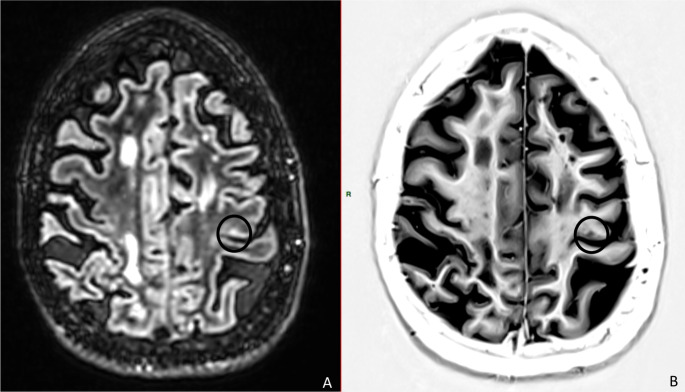

Multiple sclerosis (MS) is a central nervous system disease involving gray and white matters. Transcranial magnetic stimulation (TMS) and magnetic resonance imaging (MRI) could help identify potential markers of disease evolution, disability, and treatment response. This work evaluates the relationship between intracortical inhibition and facilitation, motor cortex lesions, and corticospinal tract (CST) integrity. Consecutive adult patients with progressive MS were included. Sociodemographic and clinical data were collected. MRI was acquired to assess primary motor cortex lesions (double inversion and phase-sensitive inversion recovery) and CST integrity (diffusion tensor imaging). TMS outcomes were obtained: motor evoked potentials (MEP) latency, resting motor threshold, short-interval intracortical facilitation (ICF) and inhibition. Correlation analysis was performed. Twenty-five patients completed the study (13 females, age: 55.60 ± 11.49 years, Expanded Disability Status Score: 6.00 ± 1.25). Inverse correlations were found between ICF mean and each of CST radial diffusivity (RD) (ρ =-0.56; p < 0.01), CST apparent diffusion coefficient (ADC) (ρ=-0.44; p = 0.03), and disease duration (ρ=-0.46; p = 0.02). MEP latencies were directly correlated with disability scores (ρ = 0.55; p < 0.01). High ADC/RD and low ICF have been previously reported in patients with MS. While the former could reflect structural damage of the CST, the latter could hint towards an aberrant synaptic transmission as well as a depletion of facilitatory compensatory mechanisms that helps overcoming functional decline. The findings suggest concomitant structural and functional abnormalities at later disease stages that would be accompanied with a heightened disability. The results should be interpreted with caution mainly because of the small sample size that precludes further comparisons (e.g., treated vs. untreated patients, primary vs. secondary progressive MS). The role of these outcomes as potential MS biomarkers merit to be further explored.

Abstract Image